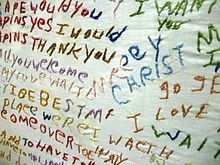

A person diagnosed with schizophrenia may experience hallucinations (most reported are hearing voices), delusions (often bizarre or persecutory in nature), and disorganized thinking and speech. The latter may range from loss of train of thought, to sentences only loosely connected in meaning, to incoherence known as word salad in severe cases. Social withdrawal, sloppiness of dress and hygiene, and loss of motivation and judgment are all common in schizophrenia. There is often an observable pattern of emotional difficulty, for example lack of responsiveness. Impairment in social cognition is associated with schizophrenia, as are symptoms of paranoia; social isolation commonly occurs. Difficulties in working and long-term memory, attention, executive functioning, and speed of processing also commonly occur. In one uncommon subtype, the person may be largely mute, remain motionless in bizarre postures, or exhibit purposeless agitation, all signs of catatonia.